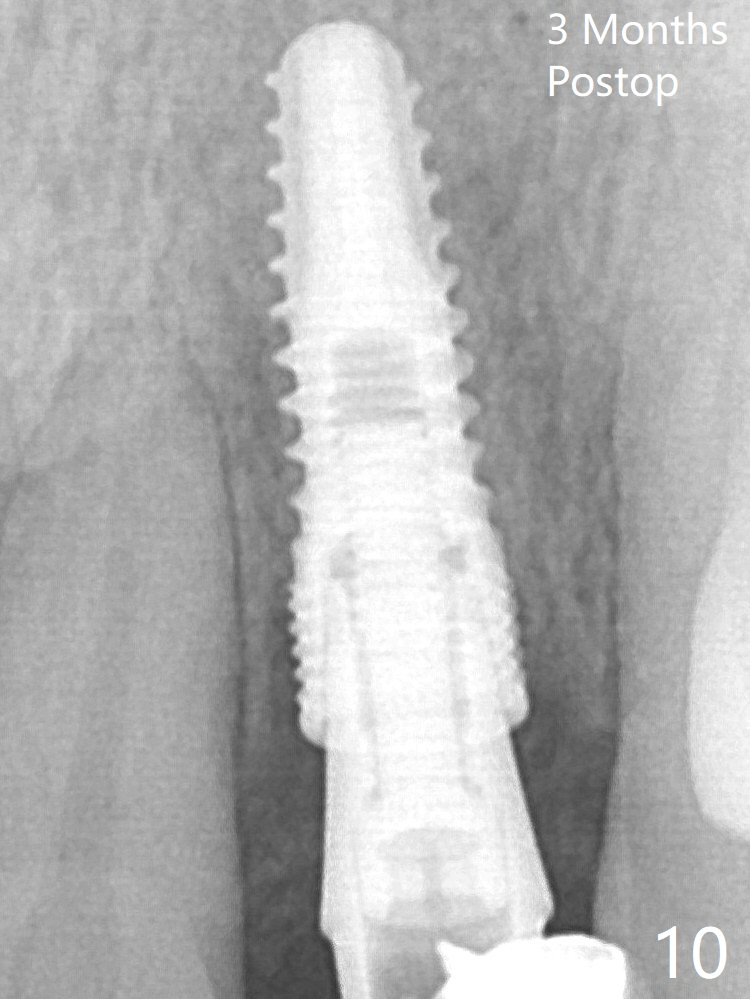

After a 3.8x12 mm SM implant is placed (Fig.4), allograft is packed in the periimplant space (*). The patient returns for impression 3.5 months postop (Fig.10).